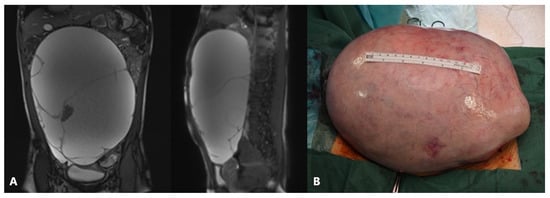

Adolescent ovaries can have several follicles at various developmental stages. The majority of ovarian cysts in adolescents are follicular cysts, which occur due to a maturing follicle’s failure to ovulate and involute. Large cysts can lead to frequent urination, constipation, or a sensation of pressure in the lower belly, whereas twisting, rupture, or hemorrhage of the cyst causes intense acute pain (Figure 2) [46].

Figure 2.

A 13-year-old adolescent presented to the emergency room because of recurrent crampy abdominal pain that lasted a short time and then subsided. She had had the symptoms for about a week. An abdominal ultrasound was performed, which showed a mass in the pelvis. (A) MSCT of the abdomen revealed a 9.1 × 8.8 cm solid cystic mass in the right ovary that was not perfused; (B) Intraoperatively, a torquing, partially necrotic tumor of the ovary was noted; (C) Pathohistological findings were consistent with a mature teratoma of the right ovary. Source: Archive of the Department of Pediatric Surgery, University Hospital of Split.